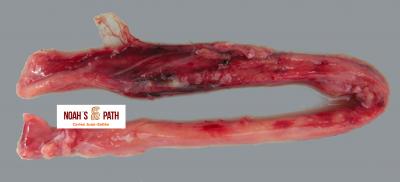

El examen post mortem ofrece una oportunidad única de acceso a todos los tejidos del paciente para diagnóstico de las causas de enfermedad y muerte, y por lo tanto es esencial para medicina preventiva y curativa en grupos de animales, seguimiento de casos, estudios sobre enfermedades, control de zoonosis, medicina de la conservación, y patología forense. En Noah's Path pensamos que un examen post mortem de este tipo de fauna debería ser realizado siempre que sea posible por patólogas/os especializadas/os con el fin de obtener el máximo de información y obtener las muestras más adecuadas.